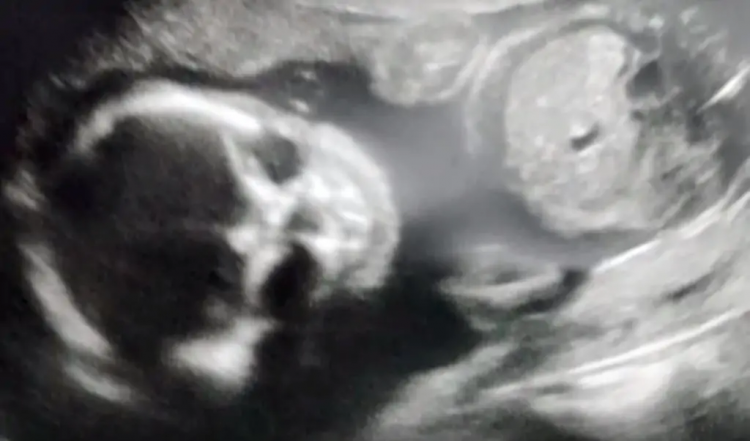

When Jessica Woods got an ultrasound done, the screen showed what seemed to be a skeletal figure growing inside of her.

Jessica said to Inside Edition: “First, it was like a normal ultrasound and it just looked like a normal baby. And then, he turned his head and that is whenever it started looking skeletal.”

The image showed the outline of a skull and it is a bit far from what parents would expect a baby boy to look like.

People don’t blame her for panicking after seeing the image. Ultrasounds usually show facial features but not like hers. Jessica even thought she might give birth to Skeletor, a fictional archenemy of He-Man in the Masters of the Universe.

Doctors told her there was nothing to worry about as the x-ray was just doing its job. It picked up the image of the underlying bone structure of her child.